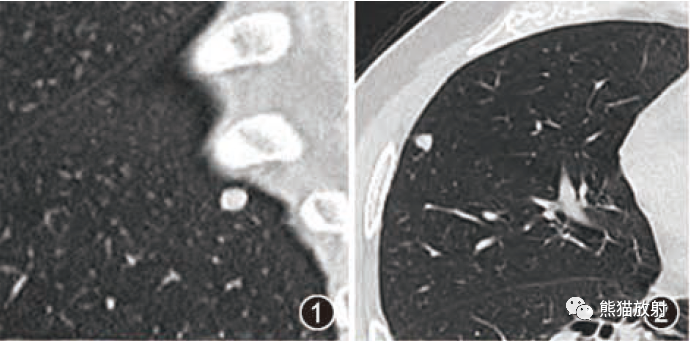

CT平扫呈稍高密度或等密度,多数境界清楚,少数与脑组织分界不清楚,肿瘤内囊变坏死较常见,但一般没有钙化。增强CT扫描肿瘤呈均质显著强化,肿瘤内囊变坏死者强化不均质。

1.肿瘤主要表现为等长T1 、等长T2 混杂信号影,偶可见短T1 或短T2 信号影,注药后,肿瘤增强明显但不均匀;

2.外形呈不规则分叶状;

3.半数以上的肿瘤与硬膜窄基底相连;

4.肿瘤内常可见血管流空影而见不到钙化影;

5.肿瘤附近骨质可见破坏而见不到增生硬化。